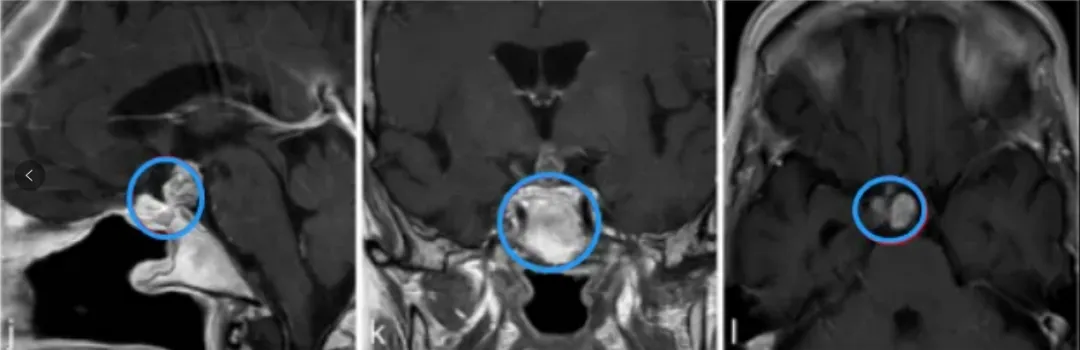

j、k、l图显示,肿瘤得到全切,术后2年无复发,目前孩子在接受激素替代疗法